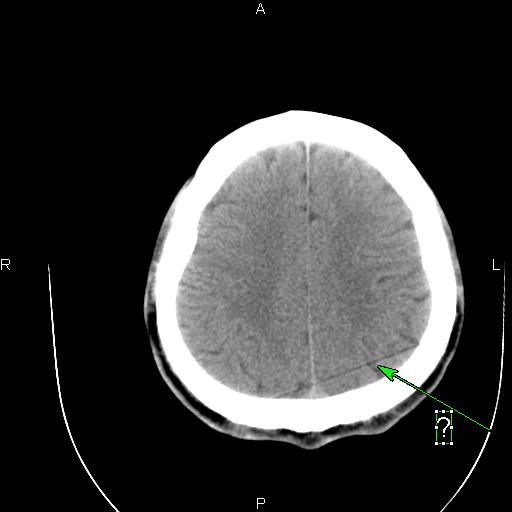

[设备故障求助] 东软ct图像伪影求助

B13F_001.jpg B13E_001.jpg B141_001.jpg B140_001.jpg

这种伪影是怎样造成的?怎样解决呢?

应该是某个通道跳起引起的直线伪影。你可以在过滤成像里检查一下,应该可以看到一跟亮线,找到是某个通道,然后屏蔽就可以了。另外一种方法就是,在ps里,不放线,不旋转,之间看所有的通道值,有没有跳起的?在ps里,放线,不旋转,这样可以看得更加清晰!你可以找到跳起的通道,或你也可以找到相应位置的das板,然后把有问题的das板换到边上,这样也可以解决问题。应该是检测器中间部位的某个das板或是通道引起的伪影